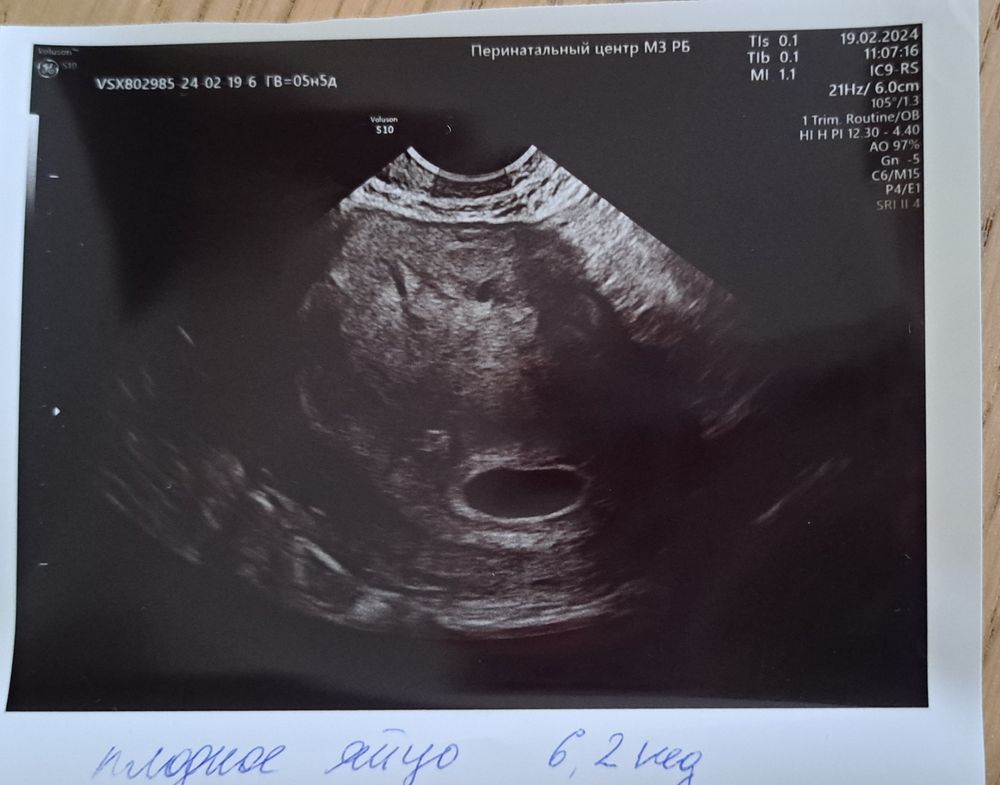

16.02 сделала узи платно для постановки беременности. Плодное яйцо 13.5, желточный мешочек 4 мм, ктр 2 мм. Срок: 4 недели. Обнаружили какое-то жидкостное содержимое в матке, не описали. Гинеколог направила сделать узи 19.02 в жк. Я сходила, но не понятно ничего: плодное яйцо 14.8, срок аш 6.2 недели, не обнаружили желточный мешочек и эмбриона + ретрохориальная гематома.

Видно, что на узи 19.02 аппарат лучше, и срок они вам рассчитали правильно (у вас 6 акушерских недель, исходя из дпм). Я бы рекомендовала к ним же через неделю, если есть возможность. Судя по размеру ПЯ, эмбрион и ЖМ еще может появится.

учитывая, что в первом месте не умеют считать срок беременности и качество не очень, я бы не сильно доверяла их данным.

Срок 6 недель - это как раз 4 эмбриональные. Как ниже написали, в 4 недели акушерские даже яйца не найдут, а если найдут, то максиму 2мм. Срок по ПЯ вам точно одинаковый поставили. Только на втором УЗИ фото лучше, видимо и аппарат мощнее. На счёт компетентности врачей сказать не могу. Переделайте УЗИ позже.